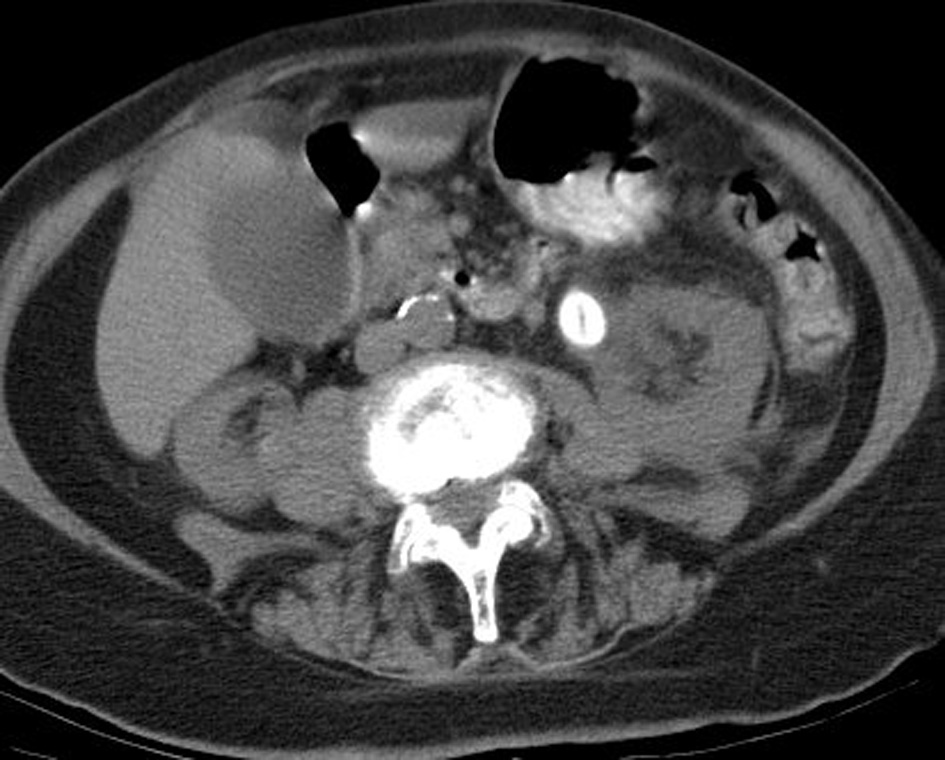

We report on an 87-year-old female who presented with recurrent, severe flank pain. Non-contrast CT revealed a 1.7 × 1.4 cm smooth, ovoid calculus in the proximal left ureter (Fig. 1). This calculus measured 272 Hounsfield units and had a linear low density center. The 5 mm thick images from a 64 slice multidetector CT scanner (CTi, General Electric Medical Systems, Milwaukee, WI) were obtained. Scanning parameters were at 120 kVp and 240 mA; 0.625 mm source images were obtained and reconstructed to 5 mm thick images for review at a PACS station. A dipstick urinalysis the 1 day prior to surgery was unremarkable, with a pH of 7. The patient underwent left PCNL for removal of the stone. During surgery, the stone was noted to be white yellow in coloration, soft and easily fragmented, and with a lamellar internal appearance. Stone analysis using infrared spectroscopy indicated that the stone was pure 2,8-DHA. The patient was discharged and has not reported further incidence of stones in 7-year follow-up.

Figure 1. CT image showing calculus. |

The calculus was in the lower range of density for uric acid stones (386 ± 154 HU) [3] and CT imaging by itself was not sufficient for discrimination between the two. It can be expected that most DHA stones will be radiolucent on plain abdominal radiographs, based both on previous reports and on the low attenuation of this stone [4]. The linear central lucency may be characteristic of DHA stones or an unusual development in this patient, but may represent a significant means of differentiation from other low density stones if observed in other patients. To be certain, additional reports of CT imaging of DHA stones are needed.